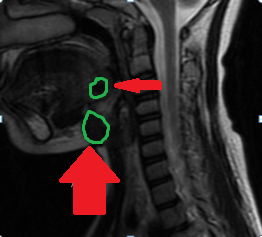

Neck SPECT/CT. Green arrow — Ectopic (within the sheath) parathyroid adenoma. Red arrow — Right common carotid artery (Courtesy Dr. V. Penopoulos)